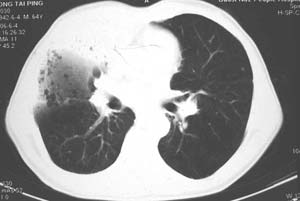

右肺上叶见片状 网格状及索条致密影.其内参杂斑点状小结节,部分融合,密度不均匀,内见含气支气管像,纵隔内见肿大淋巴结,其他肺呈代偿性肺气肿像.结合男 64  咳血,咳痰 发热 3天 血象1.2万,综合考虑:1 慢性炎症伴间质纤维化 肺气肿.2 不除外特发性感染的可能.

右肺上叶大片片状、网格状及索条致密影,前半部密实向后逐渐疏松,其内参杂斑点状小结节,密度不均匀,内见含气支气管像,纵隔内见肿大淋巴结,其他肺呈弥漫性小叶中心性性肺气肿改变,结合男 64  咳血,咳痰,发热3天,血象1.2万。考虑:1 慢性支气管炎、肺气肿合并右上肺感染。2 不除外结核合并感染的可能。

右肺上叶见片状 网格状及索条致密影.其内参杂斑点状小结节,部分融合,密度不均匀,内见含气支气管像,前段有一小片结影,纵隔内见肿大淋巴结,右侧胸腔少量积液。.结合男 64  咳血,咳痰 发热 3天 血象1.2万,综合考虑:2 右上肺感染伴间质纤维化 2 警惕细支气管肺泡癌。3建议结合临床及进一步检查[痰及纤支镜]或治疗后复查

右侧胸廓略小于左侧,右肺上叶大片实变影,近肺门处密度较高,内见支气管气相,周围较淡,呈网格状,余肺野清晰,纵隔内见肿大淋巴结,右侧胸腔少量积液。临床 咳血,咳痰 发热 , 血象1.2万。

考虑大叶性肺炎。

右侧胸阔塌陷,纵隔右移。右上肺大片状高密度影,沿支气管血管束走行,内见点状钙化;支气管充气征阳性,支气管呈柱状扩张;胸膜下小叶间隔增厚;右侧后胸壁内侧见带状水样密度影;纵隔淋巴结增大。

考虑:①右上叶陈旧性结核合并感染可能大。②右侧少量胸水。

影像学表现:右肺上叶大片状、网格状及索条致密影,前半部密实向后逐渐疏松,其内参杂斑点状小结节,密度不均匀,内见含气支气管像,纵隔内见肿大淋巴结.

综上,以右上肺tb(干酪性肺炎)首先考虑.当然大叶性肺炎不能除外.(血象不是特别高,纵隔内淋巴结肿大,也不甚支持.).如果经积极抗感染治疗,病灶明显好转.更能明确为大叶性肺炎.也不能明确排除肺ca.建议痰培养和纤支镜.

右肺上叶见片状,网格状及索条样致密影,内见支气管气相,纵隔内见肿大淋巴结,同侧胸腔内少量液性密度影,余肺呈肺气肿改变,临床:男,64岁,咳血,咳痰,发热3天,wbc---1.2万

考虑:1)右肺大叶性肺炎2)肺气肿